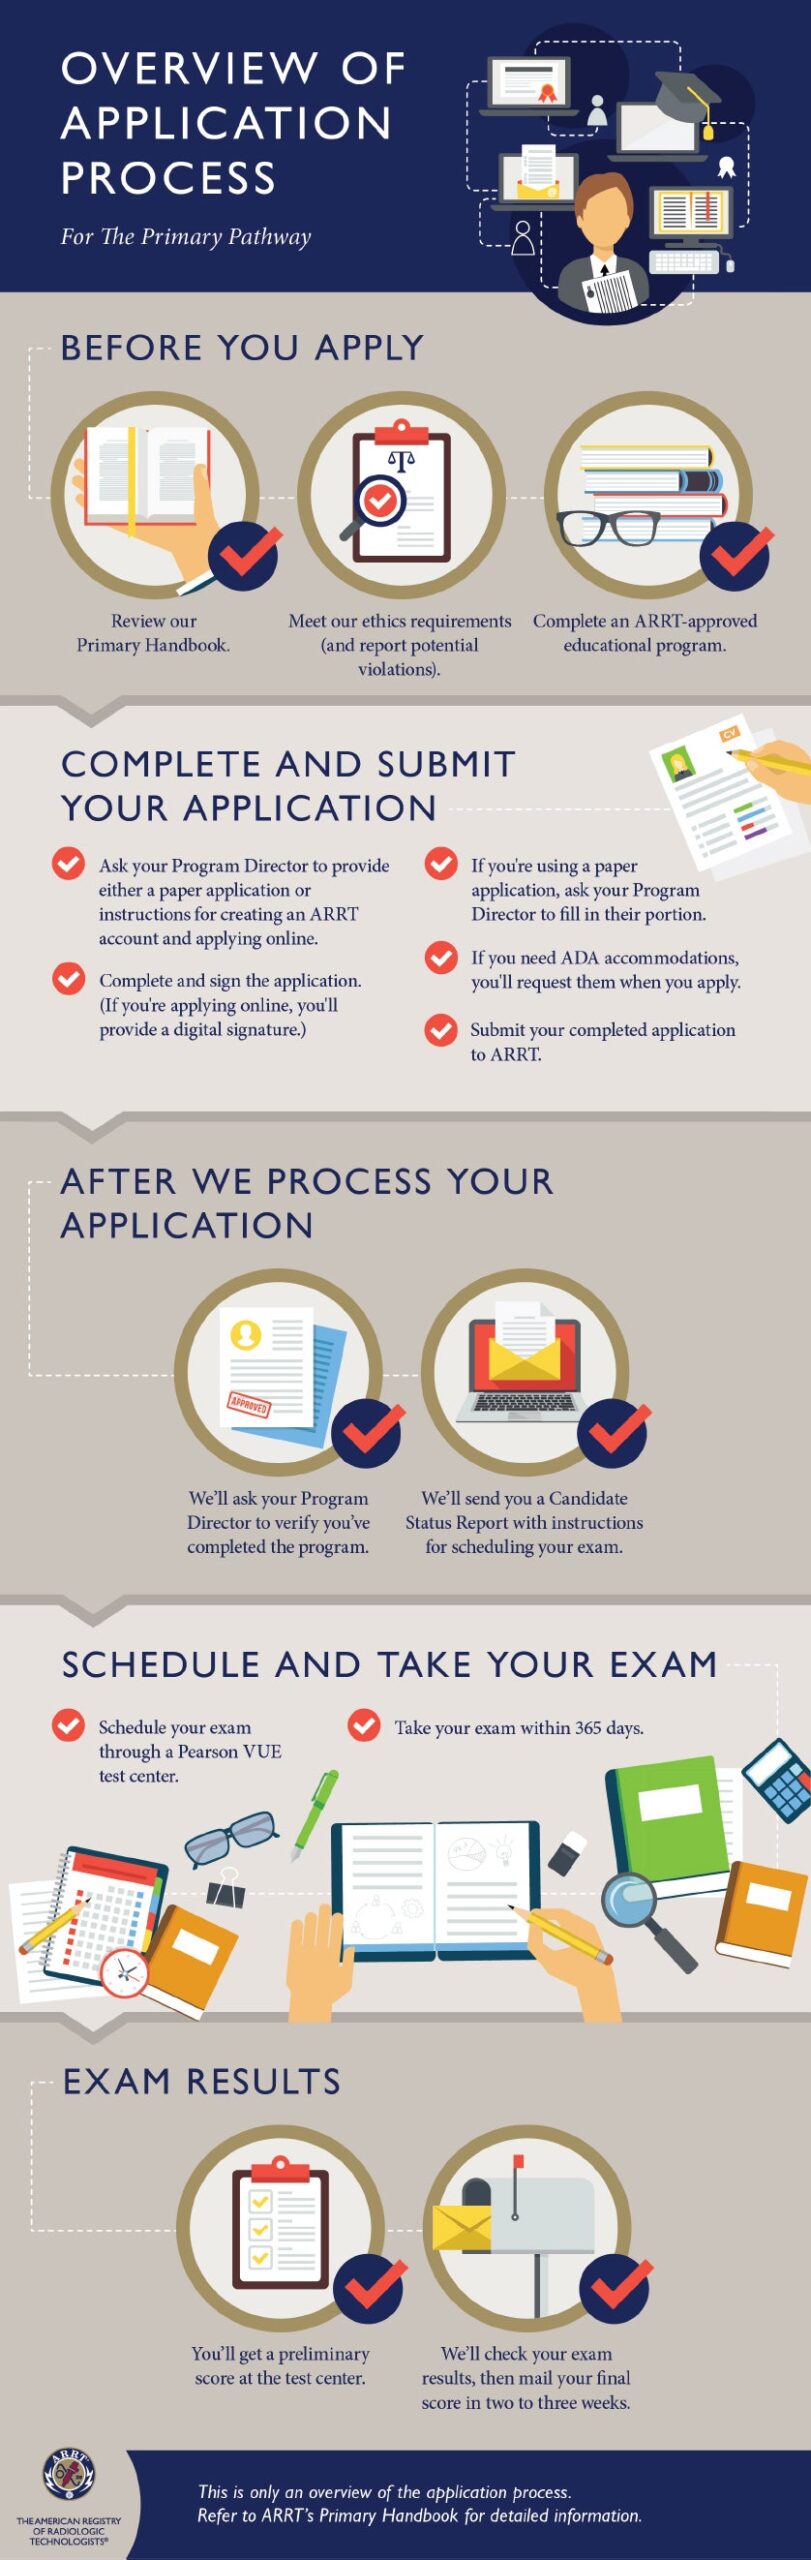

Arrt Radiography Mock Test Subscription, Passing the ARRT Radiography examination is a major milestone for aspiring radiologic technologists. The exam not only evaluates technical knowledge but also tests critical thinking, patient care understanding, and radiation safety awareness. With so much …

Arrt Exam Premium Testing Environment, An ARRT exam premium testing environment refers to a high-quality, well-managed testing setting designed to support focus, comfort, and fairness. These environments are typically characterized by modern computer systems, quiet rooms, strict security protocols, and …

Arrt Exam Unlimited Mock Test Access, Preparing for the ARRT exam can feel overwhelming. With a vast syllabus, strict exam standards, and the pressure to perform well, candidates need a reliable and effective study strategy. One of the most powerful …

Arrt Exam Adaptive Learning Tests, Preparing for a professional certification can be challenging, especially in the medical imaging field. The arrt exam adaptive learning tests have become a powerful study tool for students and professionals who want a smarter, more …

Arrt Exam Pro Mock Test Package, Preparing for the ARRT (American Registry of Radiologic Technologists) exam can be challenging. The exam not only tests your technical knowledge but also evaluates your ability to apply concepts in real clinical scenarios. This …